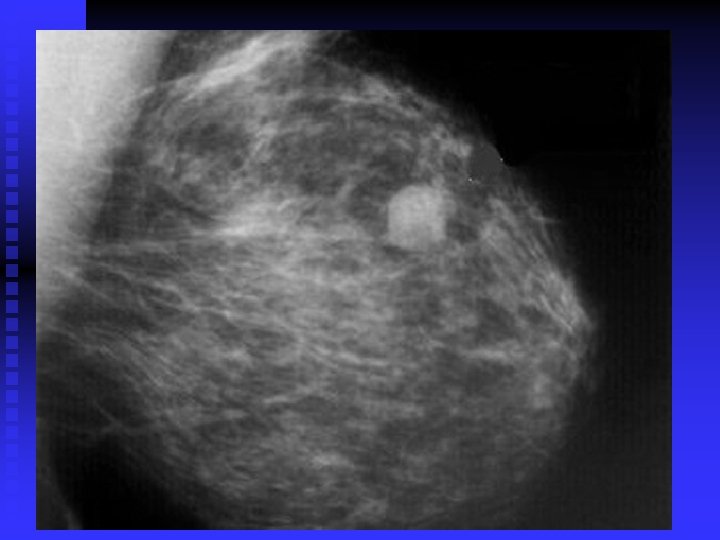

importance of high-quality mammograms is evident in the two images of the same breast